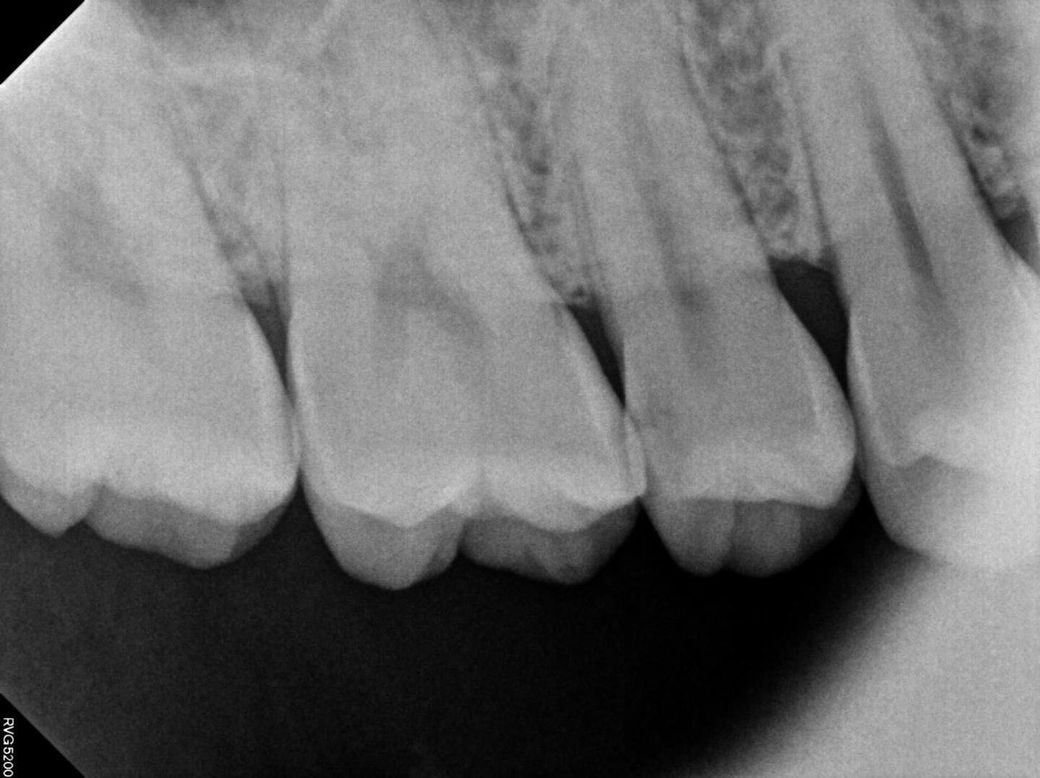

• 2번 째 사진

첫번째 사진이에 보이는 치아 2개는 치아 사이에 충치가 있는거 같습니다. 꽤 깊어 보이니 인레이 또는 신경치료 가능성도 있어 보입니다.